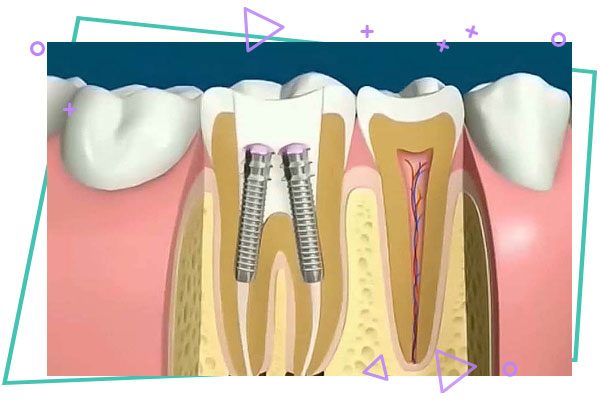

پست کور یا post core چیست ؟

معمولا در اثر وسعت پوسیدگی های دندان هایی که نیاز به درمان ریشه دارد و تخریب دندان در صورتی که ۵۰% بافت دندان بعد از برداشت پوسیدگی در تاج دندان از دست رفته باشد ، نیاز به درمان پست می باشد . پست ها به دو نوع ریختگی و پست فایبر post fiber تقسیم می گردند . در پست ریختگی بعد از برداشت قسمت های نازک تاج ، ریشه دندان تا حدی تخلیه و قالبگیری می گردد و قالب فوق به لابراتوار ارسال می شود . سازه ای فلزی به صورت یکپارچه که شامل قالب ریشه مورد نظر و تاج بازسازی شده در لابراتوار ساخته می شود که به postcore معروف است ، پست مورد نظر بعد از ارسال در دهان ، داخل دندان نصب می گردد و دندان جهت درمان روکش آماده می شود .

درمان post core ریختگی روشی عالی و موثر در دندان های به شدت تخریب شده جهت بازسازی زیر روکش و استحکام دندان می باشد .

در دندان های با تخریب کمتر می توان از پست فایبر استفاده کرد که دیگر نیازی به قالب گیری و ارسال به لابراتوار نیست .

در همان جلسه ریشه تا حدی تخلیه و فایبر پست در داخل ریشه دندان نصب شده و تاج روی آن با مواد مخصوص بازسازی می گردد و دندان جهت درمان روکش آماده می گردد .